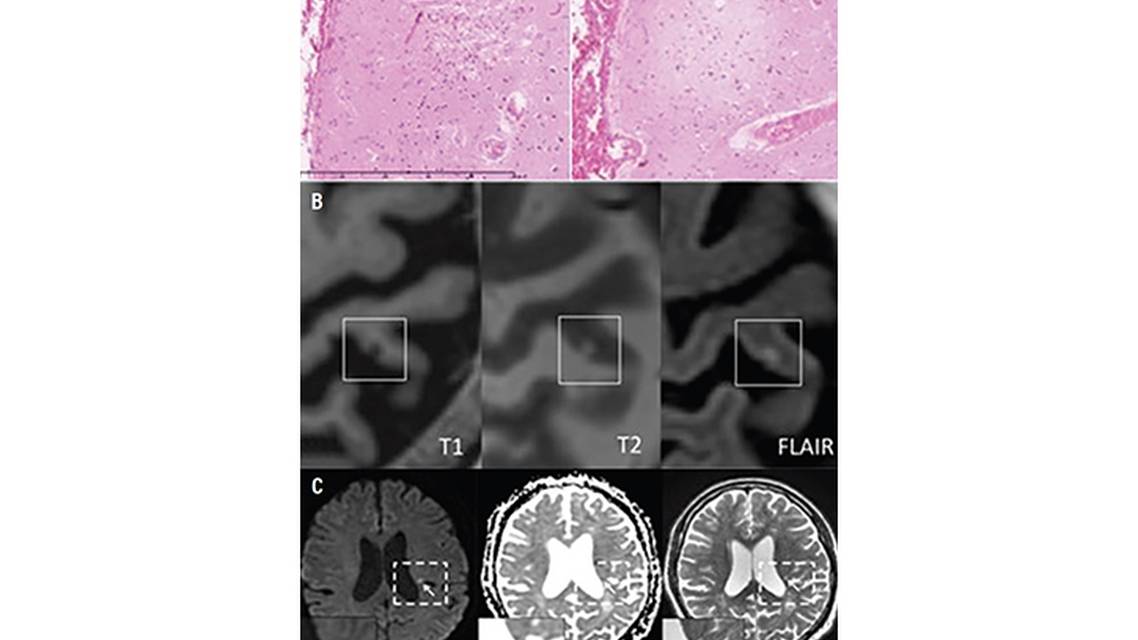

CMIs can be detected by 3 modalities: postmortem histopathologic examination, structural high-field-strength (3T or 7T) MRI, or DWI. These modalities differ with regards to the proposed size (microscopic or larger), spatial resolution (whole brain coverage or selected brain regions), and temporal resolution (acute or chronic ischemic phase).1,3 See the Table for a schematic overview and the Figure for examples of microinfarcts using these 3 modalities.

On histopathologic evaluation, CMIs as small as 50 µm can be detected in both the cortex and subcortical brain regions. Both acute CMIs (ie, displaying histopathologic characteristics of recent infarction, including tissue pallor with evidence of eosinophilic necrosis or “red” neurons) and chronic CMIs (ie, cell loss with cavitation or “puckering”) can be detected.4 This method does not indicate complete brain burden; it only provides an indication of CMI presence in a limited number of brain regions.

Structural high-field-strength MRI allows for detection of CMIs between 0.5 and 4 mm. CMIs can also be found in the acute (within hours on T2-weighted images, within days on T1-weighted images) or chronic stage with structural high-field-strength MRI. CMIs are hypointense on T1-weighted images; hyperintense on T2-weighted images; and hyperintense, isointense, or cavitated on fluid-attenuated inversion recovery images.1,3 Thus far, CMIs are defined to be strictly cortical, because it is otherwise difficult to distinguish them from subcortical lesions, such as white matter hyperintensities, lacunar infarcts, and enlarged perivascular spaces.1,5

DWI can detect CMIs up to 5 mm, but solely in the acute phase (ie, <2 weeks of onset).1 CMIs appear as hyperintense small subcortical lesions with a corresponding hypointense or isointense signal on apparent diffusion coefficient maps. This technique allows for detection of both cortical and subcortical infarcts. In the recent Standards for Reporting Vascular Changes on Neuroimaging 2 (STRIVE-2) criteria, the recommended term for these infarcts is “incidental DWI-positive lesions”.3 Recently, serial DWI found that none of these “acute CMIs” were retraceable on follow-up imaging as chronic CMIs.6 CMIs differ between these modalities to such an extent that they cannot be readily compared, and whether they are to be classified as a single lesion type at all is uncertain. Each modality provides a different perspective on CMI etiology and prognosis.